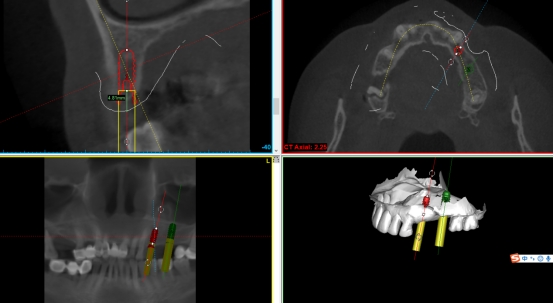

数字化种植导板是通过导板设计软件对CBCT、口扫等一系列数据的系统性分析,辅助口腔种植位点的设计,然后通过3D打印技术等途径进行导板生产,从而实现精准定位的种植手术装置。

简单来讲,数字化种植外科导板(简称导板),是将术前软件设计的种植方案,精确转移至患者口内的个性化手术辅助配件。

第三步:植入及导板设计

在数字化种植导板下,通过CBCT、口扫等途径获取口腔三维信息内容。使患者在种植之前就可以了解到种植方案的相关细节,清晰地看到牙齿修复之后的模拟展示图,提前预知种植术后的效果。

二、精准控制 更安全

在数字化种植导板下的外科手术更加精准。种植体植入方向、位置、角度、深度等一目了然,即可将种植体精准植入到最佳位置,获得更优异的临床效果,手术安全性更高。